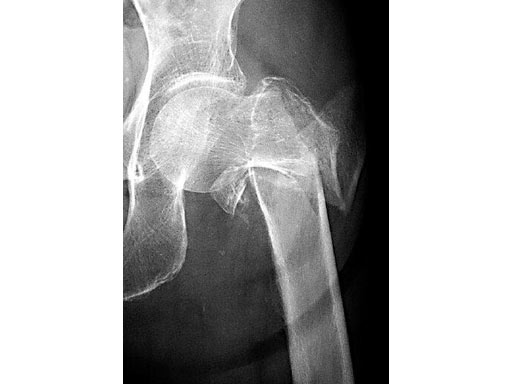

79-year-old woman.